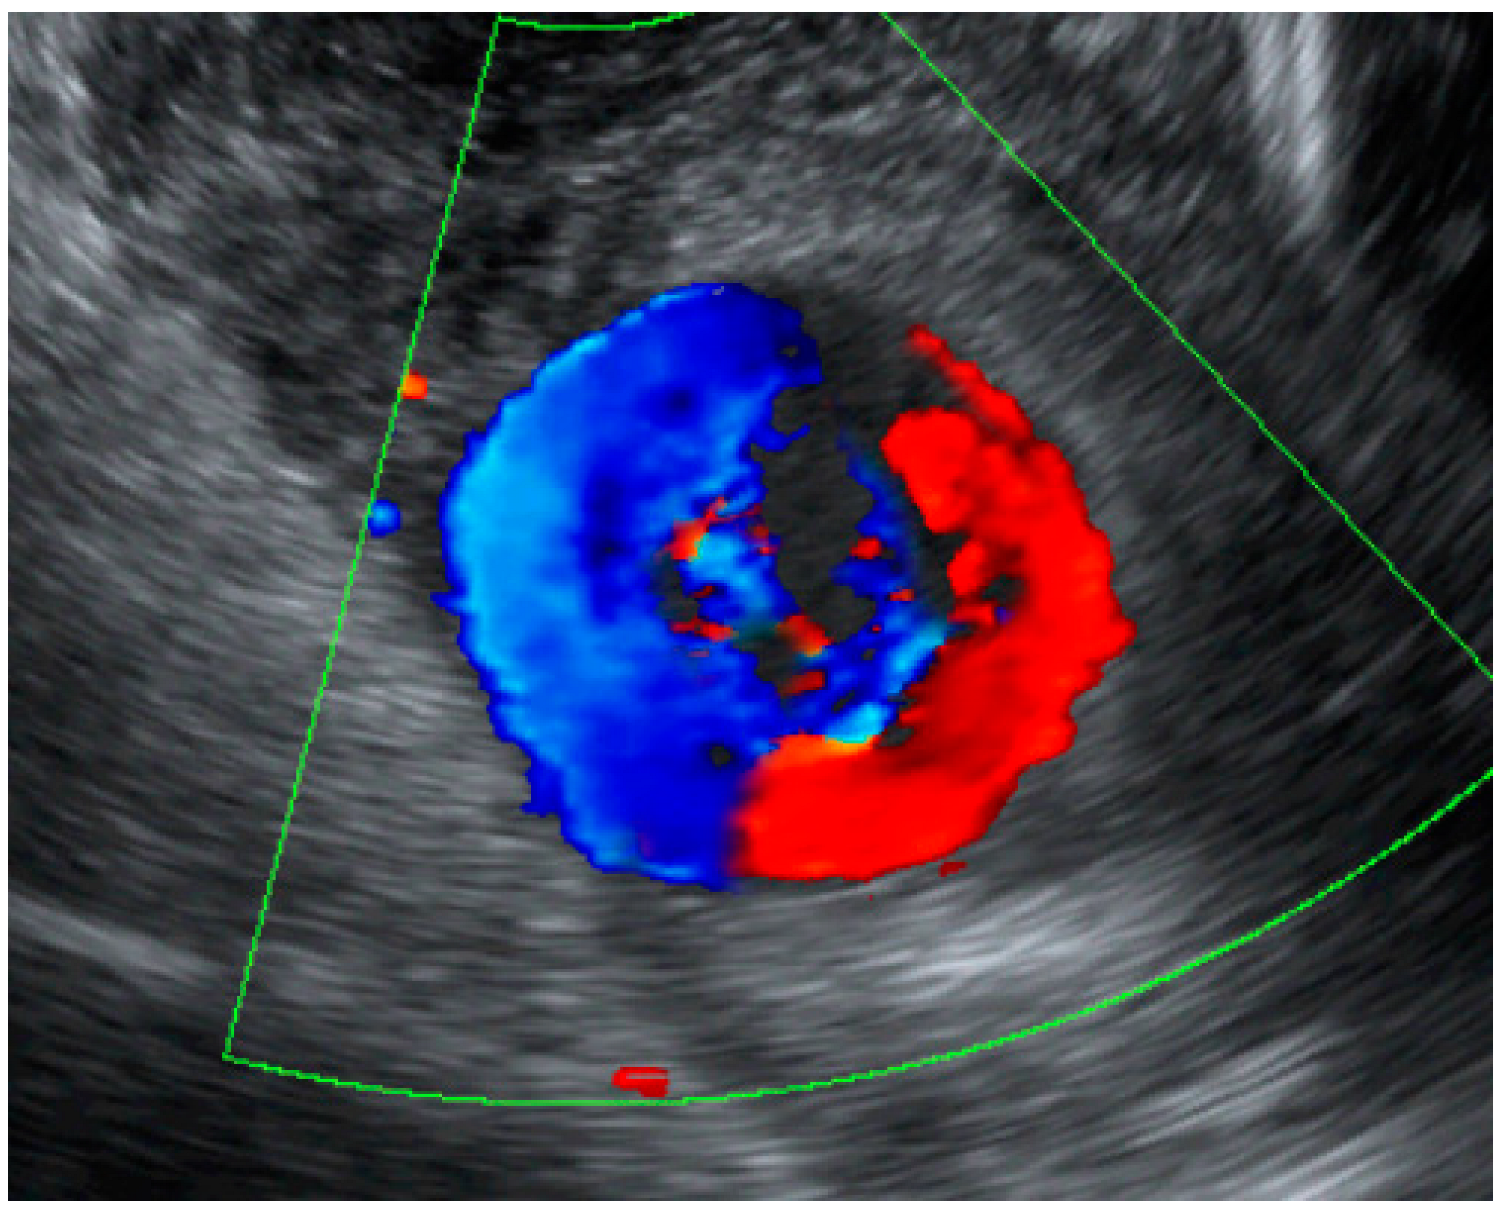

An Unruptured True Aneurysm of the Uterine Artery during Pregnancy